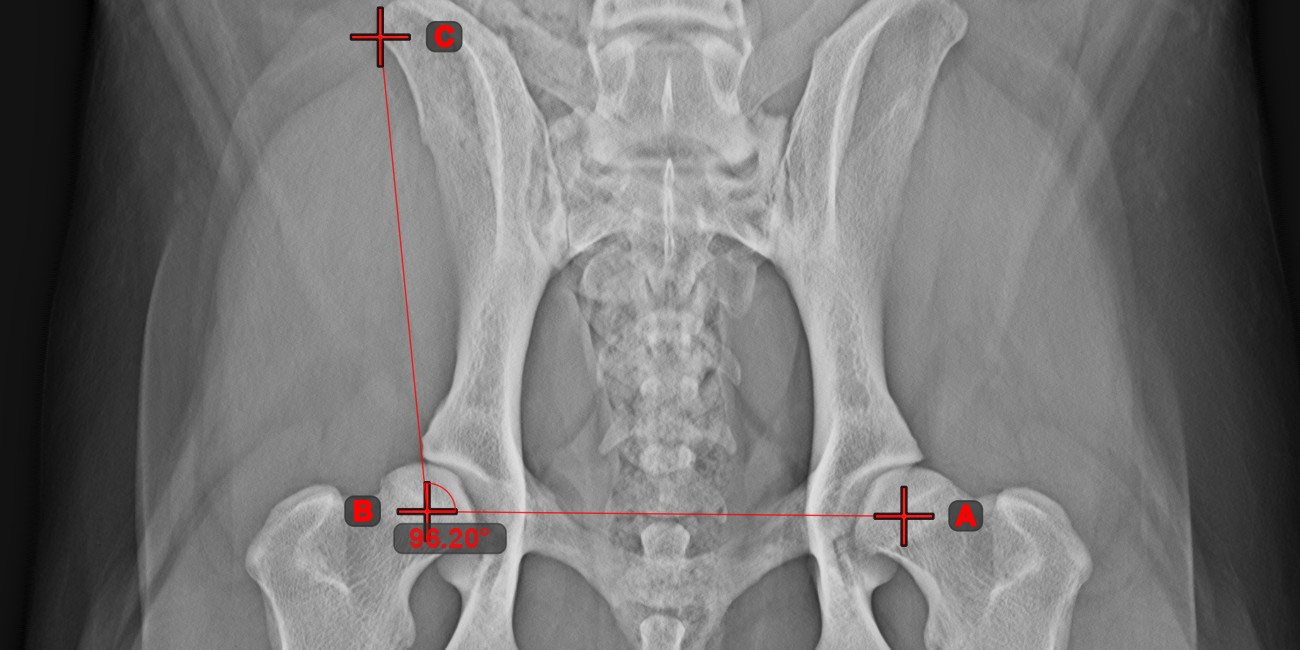

Winkel aus 3 Punkten¶

Das Werkzeug Winkel aus 3 Punkten ist eine einfache und effektive Möglichkeit, einen Winkel anhand von nur drei Punkten zu berechnen.

Beginnen Sie, indem Sie das Werkzeug aus der linken Symbolleiste auswählen und einer der verfügbaren Maustasten zuweisen. Setzen Sie den Startpunkt der Anfangsseite, den Scheitelpunkt und den Endpunkt der Endseite des Winkels oder wählen Sie die Punkte aus der Szene aus. Die Seiten des Winkels werden automatisch konstruiert, wodurch der Winkel zwischen den Linien berechnet wird.

Ändern Sie die Position der drei Punkte, um den Bogen des Winkels mit dem Werkzeug Objekt auswählen/verschieben zu ändern.